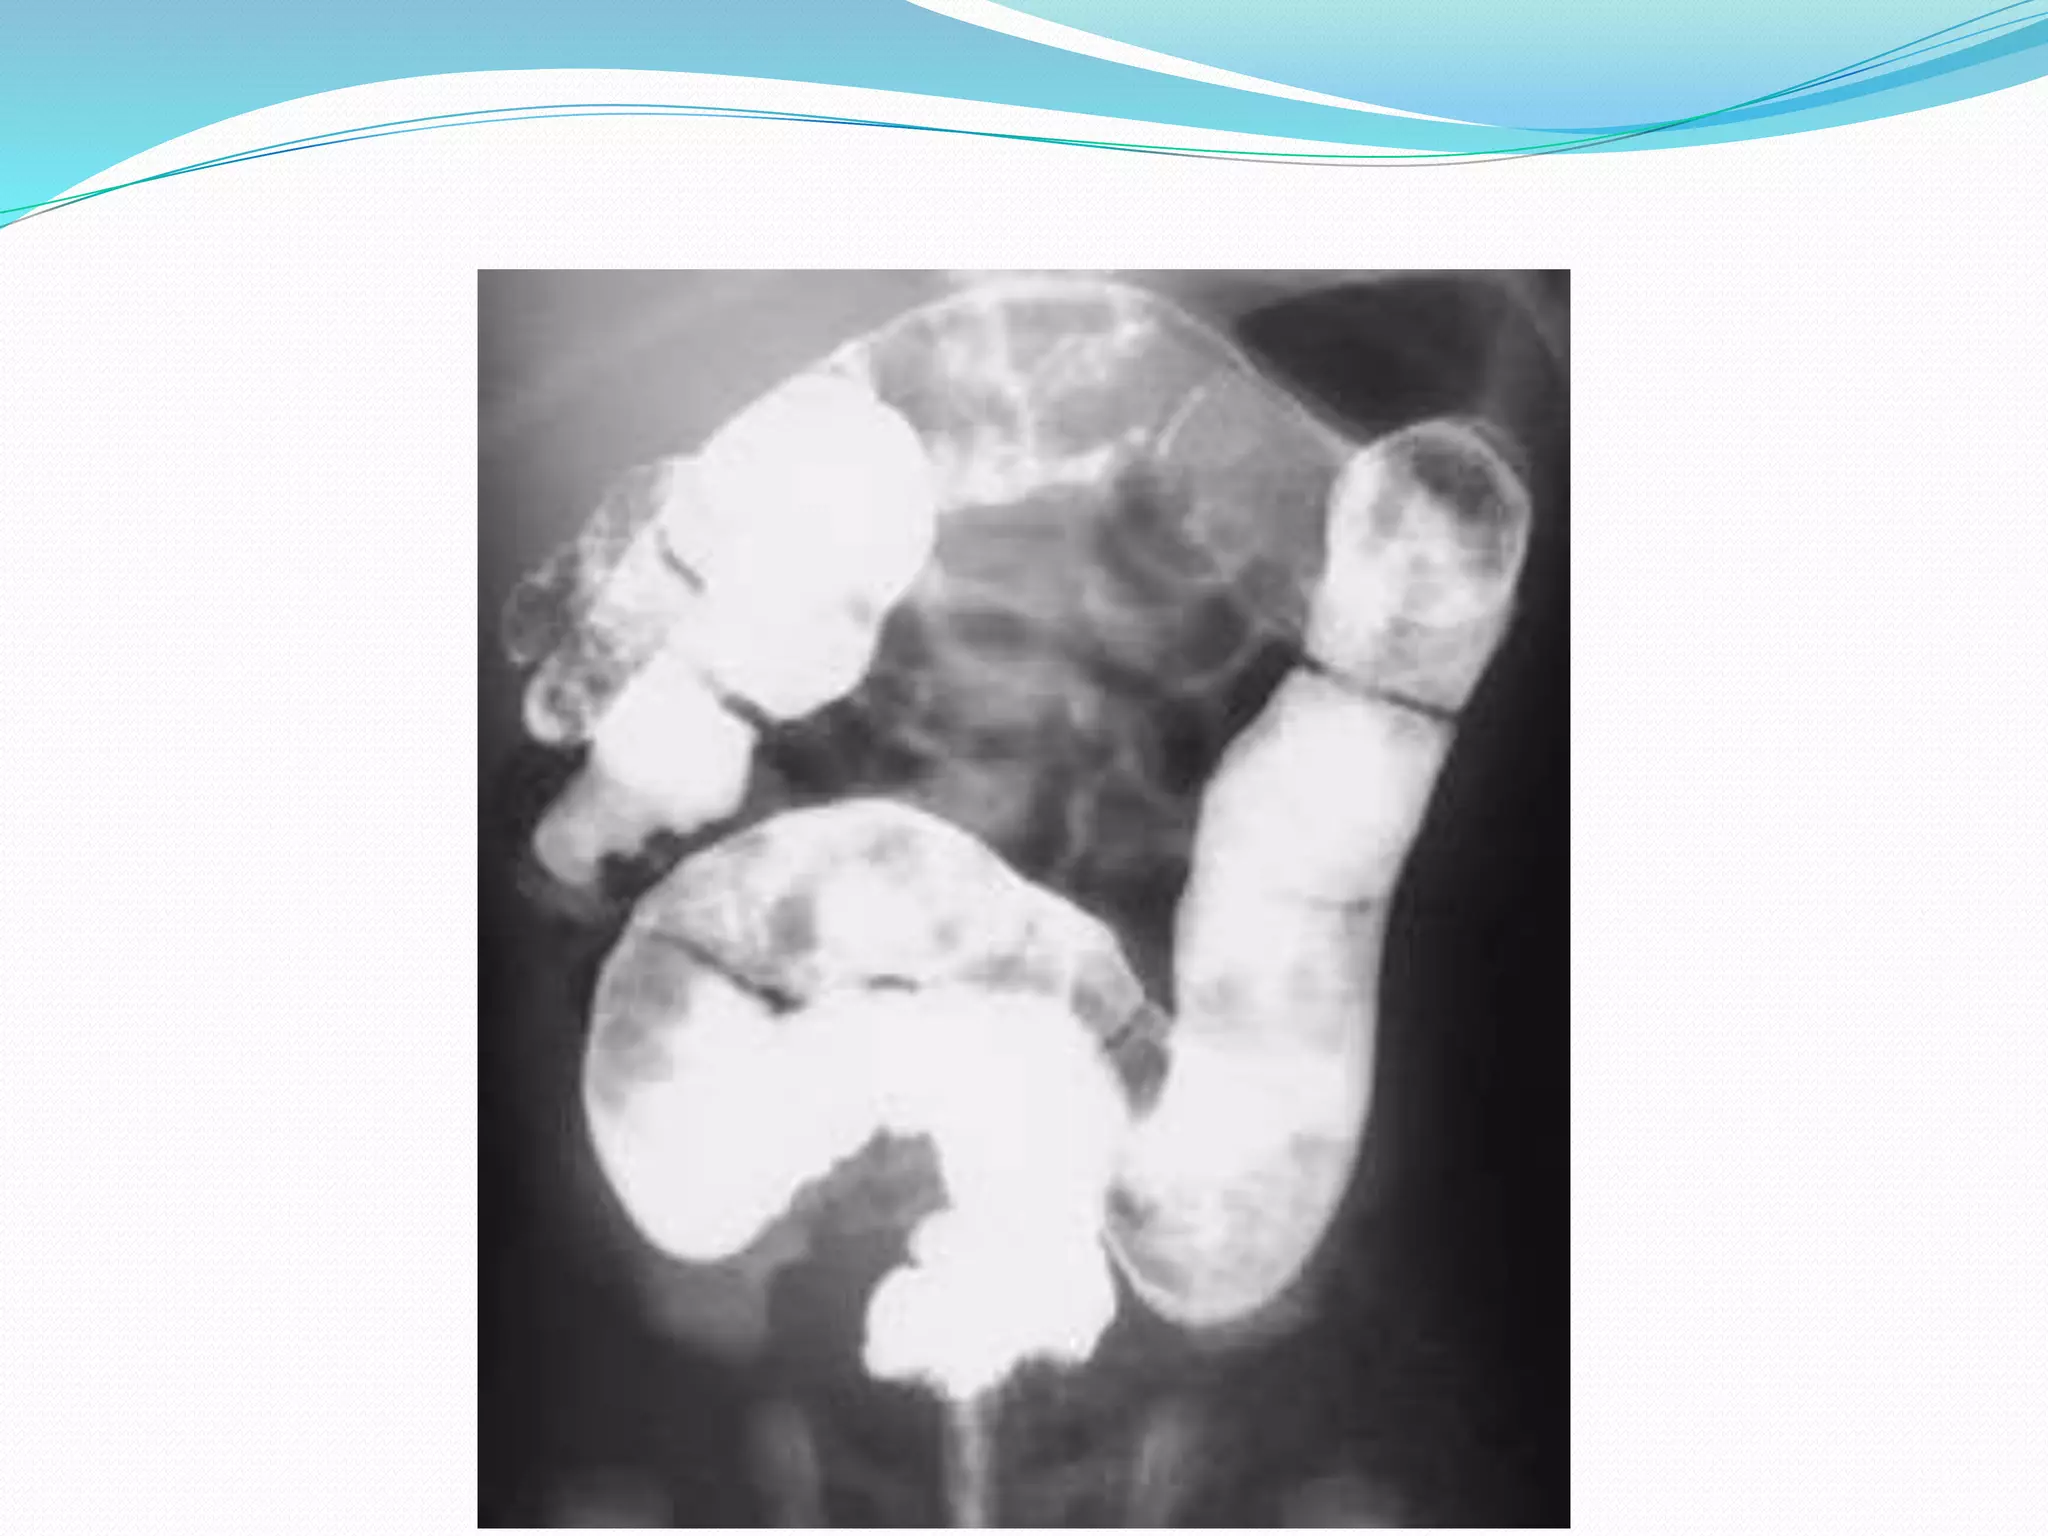

 Abdominal X-Ray…

 Barium Enema…

Day 1 6th Week Showing Transition Zone

 The Presence Of Barium In The 24-hour Delayed Film

Also Suggests Hirschsprung's Disease.

Day 1 6thWeek Showing Transition Zone

 The PresenceOf Barium In The 24-hour Delayed Film Also Suggests Hirschsprung's Disease.